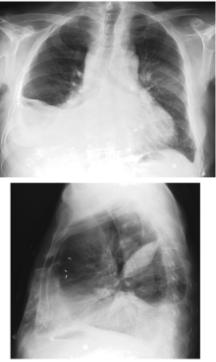

Рентгенологічне обстеження. Метод, який найчастіше застосовується у клінічній практиці і базується на просвічуванні окремих частин тіла рентгенівськими променями за рентгенівським екраном (рентгеноскопія). На екрані можна побачити тіні різної прозорості: на фоні прозорих легень можна виявляти ділянки ущільнення легеневої тканини, визначати розміри і конфігурацію серця. Для фіксації виявлених змін проводять рентгенографію - знімають зображення на плівку, що засвічується рентгенівськими променями. На рентгенівській плівці отримують негативне зображення (світлі на рентгенівському екрані місця на плівці - темні і навпаки).

Р ентгенографія є найбільш розповсюдженим методом в клінічній практиці, який дає первинну об’єктивну і задокументовану інформацію. При цьому треба пам’ятати, що рентгенограма грудної клітки є площинним зображенням складного об’ємного об’єкту. Для правильної її інтерпретації необхідно врахувати багато факторів: особливості проекційного зображення органів грудної клітки, закономірності утворення рентгенологічної картини патологічних змін в легенях і середостінні, технічні фактори і т. п.